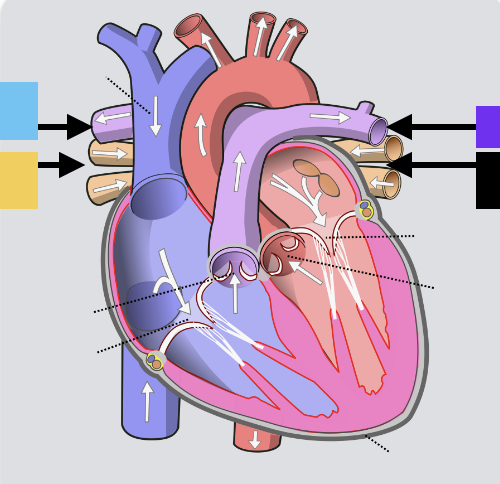

light purple

base

purple

apex

grey

right atrium

pink

right auricle

green

left atrium

green

left auricle

blue

right ventricle

orange

left ventricle

green

coronary (atrioventricular) sulcus

pink

interatrial septum

dark blue

interventricular septum

green

anterior interventricular sulcus

green

posterior interventricular sulcus

orange

aortic valve

yellow

pulmonary valve

red

tricuspid valve (right AV)

purple

bicuspid valve (left AV)

yellow

chordae tendineae

orange

papillary m.

blue

trabeculae carneae - only in ventricles

red

pectinate m. - only in R atrium

pink

fossa ovalis

grey

opening of coronary sinus

green

ligamentum arteriosum

green

fibrous pericardium

blue

parietal pericardium

pink

visceral pericardium (connective tissue) / epicardium (muscle)

purple

myocardium

grey

endocardium

pink

superior vena cava

black arrow

inferior vena cava

black

pulmonary trunk

purple

left pulmonary artery

black

left pulmonary veins

blue

(branches of) right pulmonary artery

yellow

right pulmonary veins

orange

ascending aorta

purple

aortic arch

yellow

brachiocephalic trunk (blue)

pink

right common carotid artery

purple

right subclavian artery

red

left common carotid artery (grey)

green

left subclavian artery (black)

blue

descending aorta

blue

thoracic aorta

yellow

abdominal aorta

red

right coronary artery

yellow

posterior interventricular artery

green

left coronary artery

blue

anterior interventricular artery

pink

circumflex artery

coronary sinus